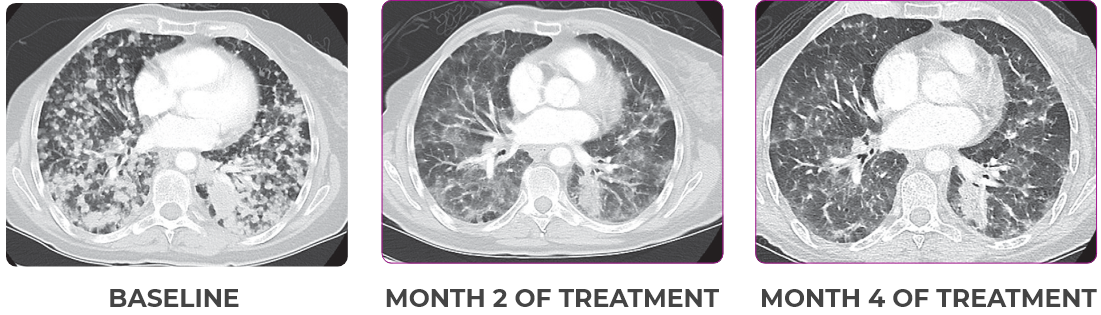

76-YEAR-OLD FEMALE WITH BRAIN METASTASES1

NSCLCa PATIENT WITH BRAIN

METASTASES1-3

- 76-year-old female with NSCLC that metastasized to the brain and liver

- No prior systemic treatment before trial enrollment

- PRa of primary lung nodules to VITRAKVI® (larotrectinib) confirmed at 2 months1

Response to VITRAKVI1,2

- Partial response to treatment that was confirmed at 2 months (34% tumor reduction)

- Grade 1 cough and Grade 2 fatigue

- Patient remains on VITRAKVI after more than 4 months of treatment

Response in primary and metastatic lesions1

Lung imaging of primary tumors.

SCAN 1: LUNG

SCAN 2: LUNG AND BONE